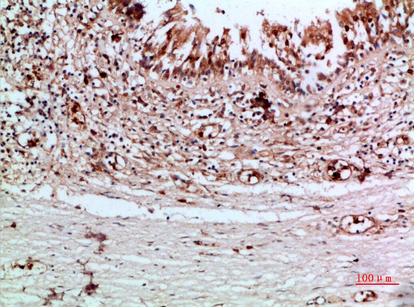

Thyroid gland specific.

Secreted. Secreted into the thyroid follicle lumen (PubMed:19509106). Localizes to colloid globules, a structure formed in the thyroid follicle lumen consisting of cross-linked TG arranged in concentric layers (PubMed:8626858, PubMed:11082042).